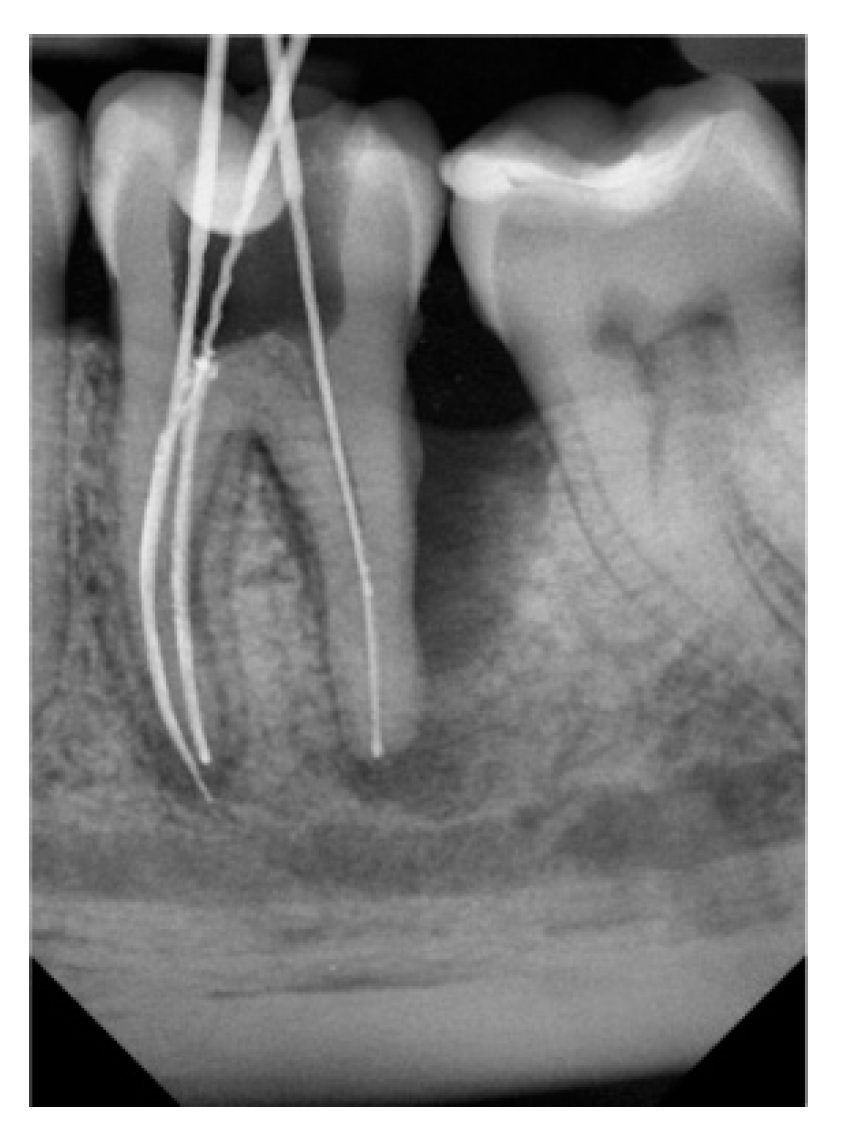

| Number of Tooth | 36 | 36 | 37 | 36 | 36 | 27 | Average Volume B/A (mm³) |

| Volume before treatment (mm³) | 654.4 | 650 | 498 | 300 | 220 | 205 | |

| Volume after treatment (mm³) | 309 | 260 | 220 | 140 | 110 | 115 | 421.23/192.3 |

| Change in percent (%) | 52.8 | 60 | 65 | 53 | 50 | 44 |

| Number of Tooth | 46 | 47 | 36 | 37 | 16 | 27 | Average Volume B/A (mm³) |

| Volume before treatment (mm³) | 287.3 | 450 | 650 | 700 | 300 | 520 | |

| Volume after treatment (mm³) | 207.1 | 310 | 400 | 580 | 245 | 360 | 484.55/350.4 |

| Change in percent (%) | 28 | 31 | 38 | 17 | 18 | 30.7 |

| Group | Amount of Teeth | Average | SD | ST p | M-W p |

|---|---|---|---|---|---|

| 1 | 6 | 192.3 | 83.0 | ||

| 2 | 6 | 350.4 | 133.1 | 0.033 | 0.037 |